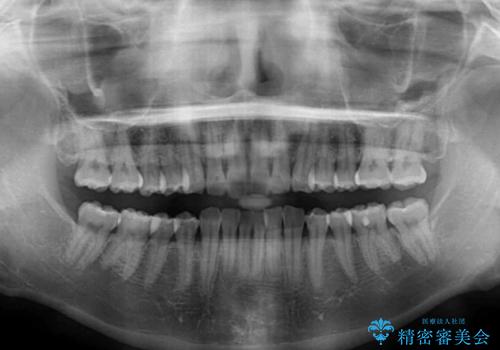

- 上下前歯の叢生を気にして来院された患者様です。

以前矯正をした後戻りということで、歯列不正はそれほど大きくなかったため、インビザライン・ライトを用いて矯正治療を行うこととしました。

前歯のデコボコが残っており、シミュレーション通りに動いていない部分がありましたが、再矯正であることやご本人の満足いくところまでデコボコが改善されたとのことで、治療を終了することとしました。